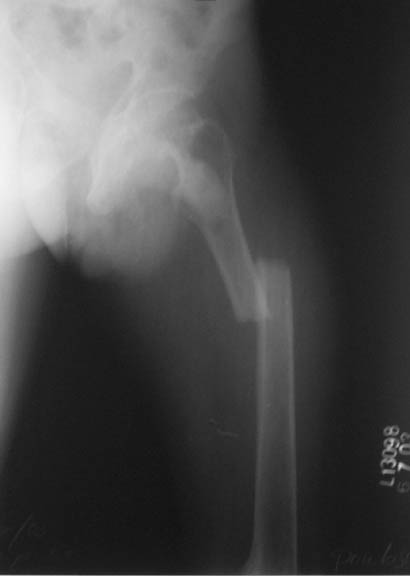

This patient,a middle aged malewas a diagnosed case of hypophosphatemic osteomalacia on treatment. Unfortunately he discontinued treatment since he was poor and also neutral phosphate was not available locally. He presented with pathological fracture of left femur and a failing neck of same femur.

We managed to get neutral phosphate, initiated medical treatment and did an antegrade SIGN nailing of left femur along with couple of screws to neck using miss a nail technique. He complained of pain of the right femur and both forearms. In OT these areas were screened using image intensifier and found that he has looser zones of all these with impending fractures. Yesterday we did a retrograde nailing of right femur usingSIGN nail. Both ulnas were stabilised usingLambrudini wires in a closed fashion. All fractures and looser zones were stabilised by closed surgery using image intensifier. It may be interesting to see the post of picture of both the hips in which one side shows an antegrade femoral SIGN nail and the other side shows a retrograde SIGN nail.